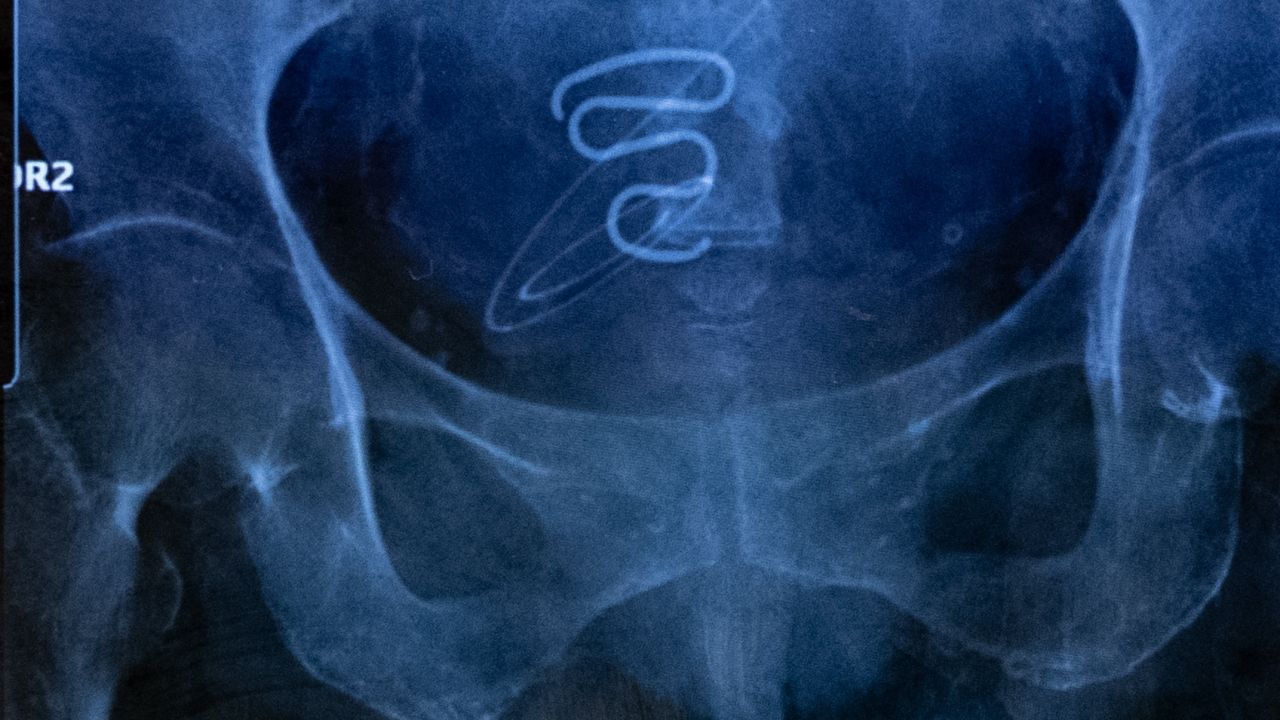

radiographie d’un stérilet spirale

Contraceptions forcées au Groenland : la fin d’un secret

De 1966 à 1975, des milliers d’Inuites, souvent mineures, se sont vu poser de force un stérilet. La photographe Juliette Pavy a recueilli leur histoire.